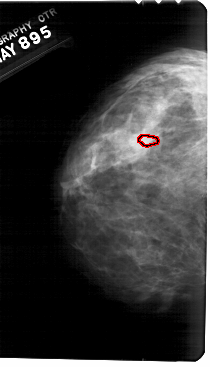

A_1685_1.LEFT_MLO

FILE: A_1685_1.LEFT_MLO.OVERLAY

TOTAL_ABNORMALITIES 1

ABNORMALITY 1

LESION_TYPE CALCIFICATION TYPE PLEOMORPHIC DISTRIBUTION CLUSTERED

ASSESSMENT 4

SUBTLETY 1

PATHOLOGY BENIGN

TOTAL_OUTLINES 1

BOUNDARY